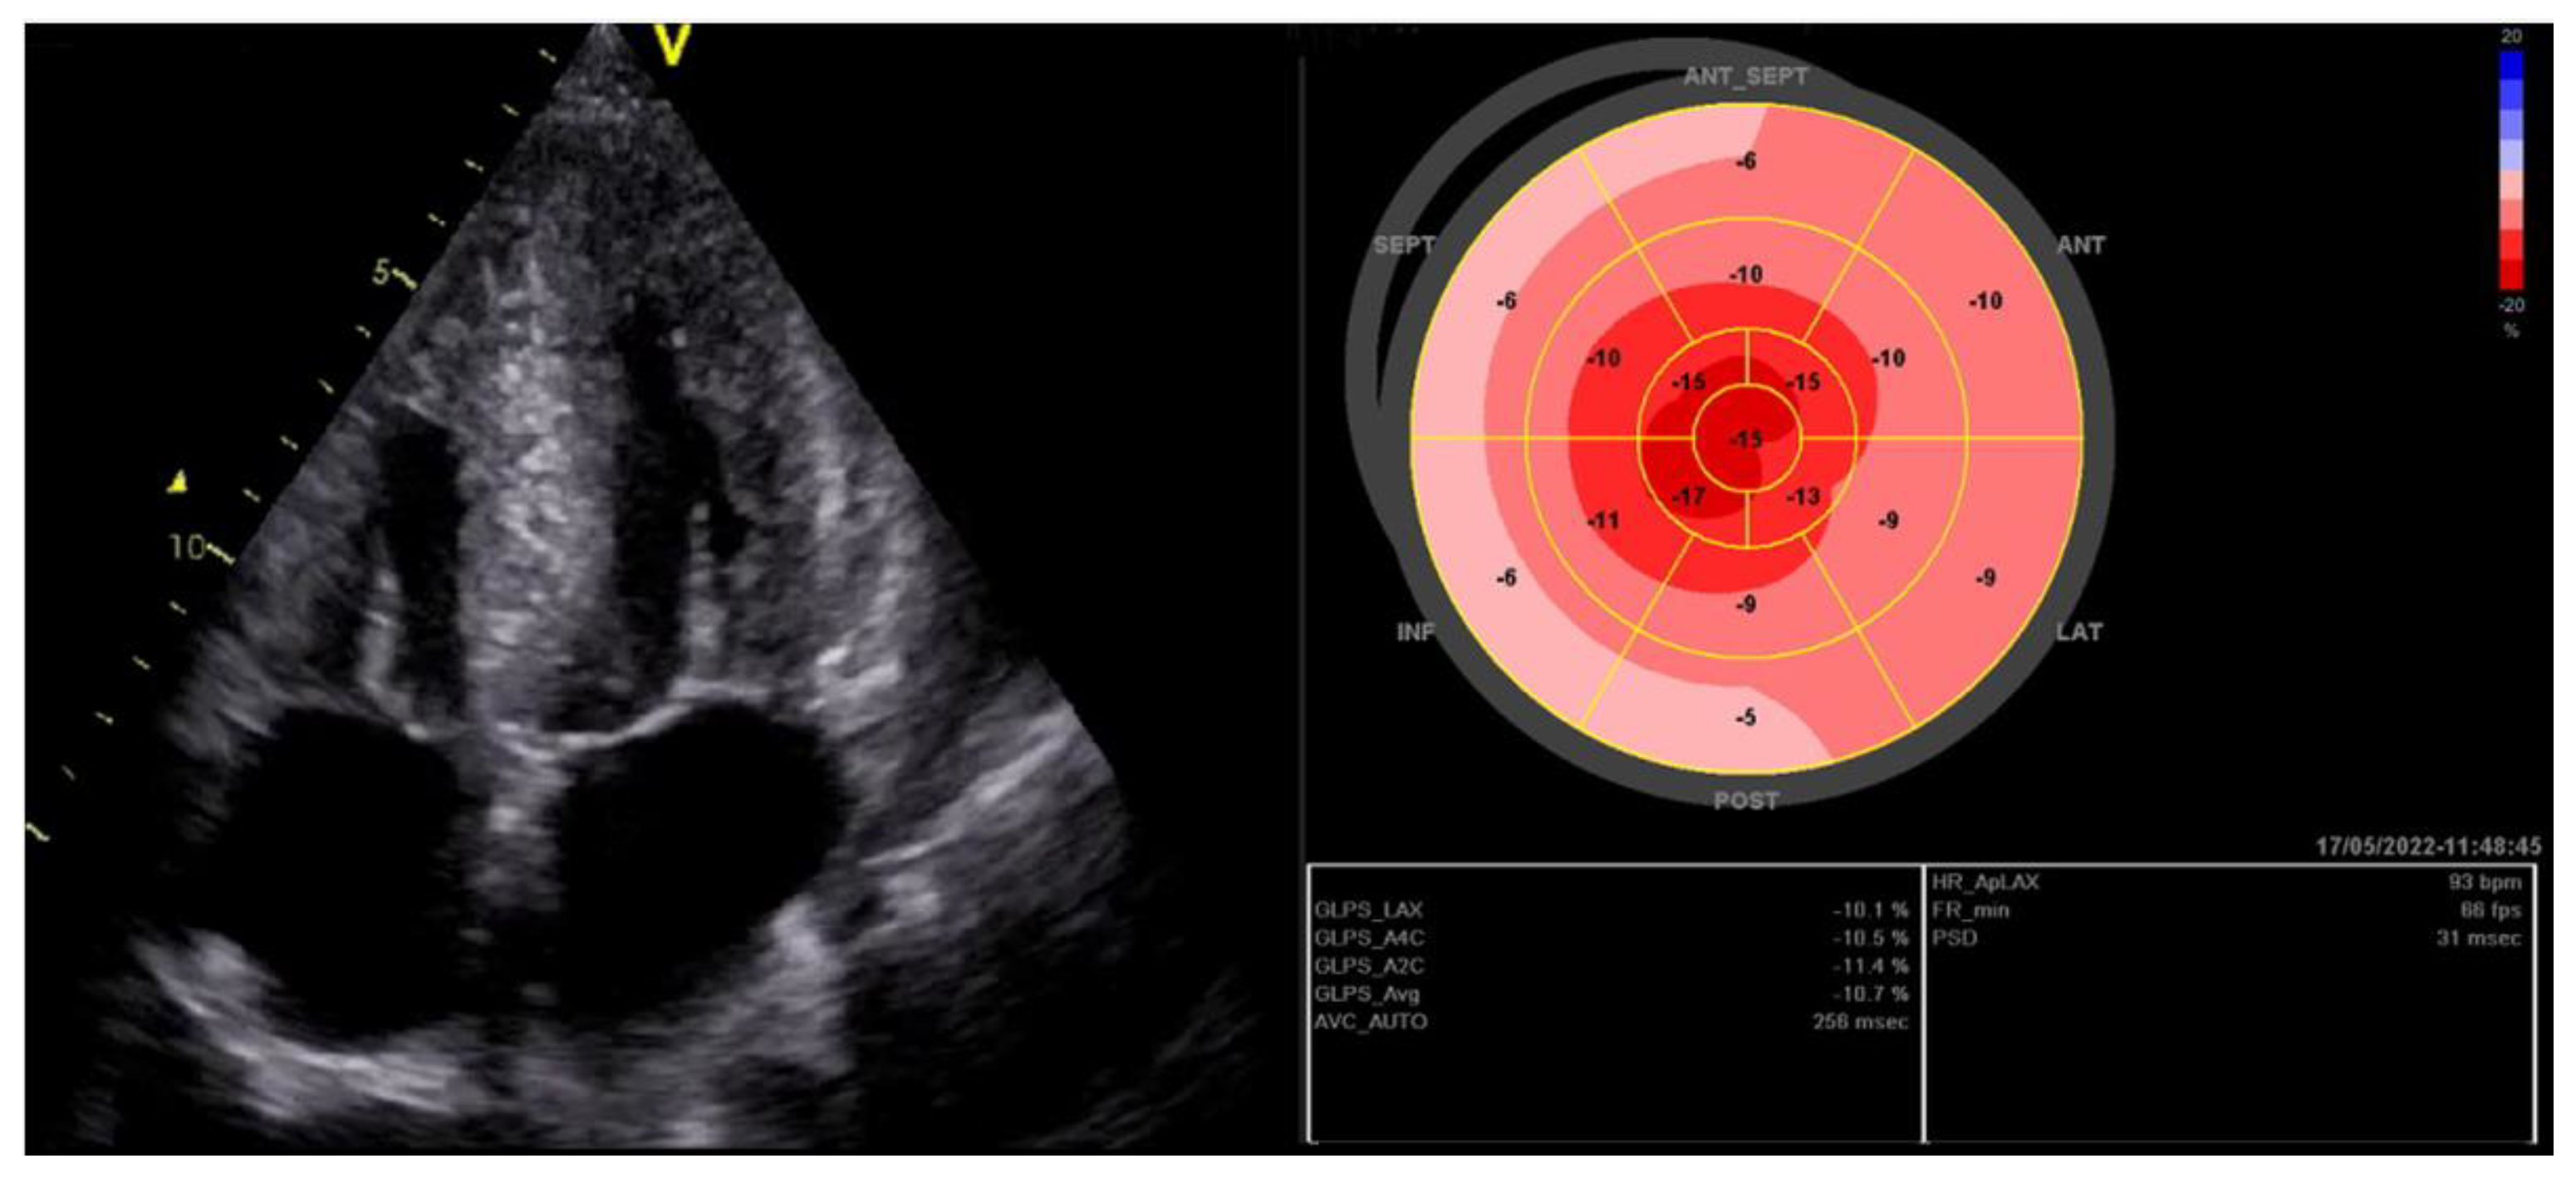

2. Global Longitudinal Strain

2.1.4. Hypertrophic Cardiomyopathy